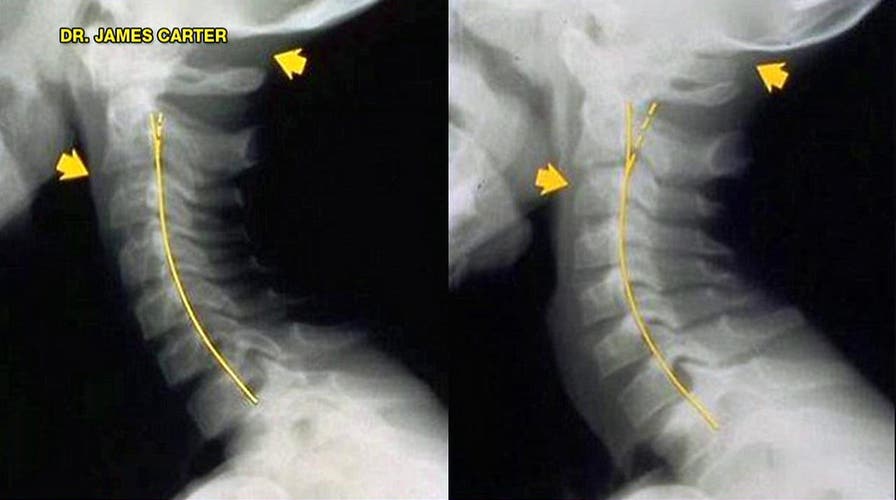

Australian chiropractor releases x-rays